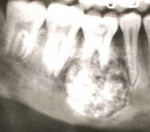

Начальная стадия развития цементомы характеризуется пролиферацией фибробластов и коллагеновых волокон в апикальной области периодонтальной связки, в результате чего возникает резорбция мозгового вещества, окружающего апекс. На данном этапе на рентгенограмме видны зоны разрежения костной ткани, имеющие большое сходство с периапикальными очагами инфекционного трансдентального происхождения. В дальнейшем во время второй стадии развития цементомы происходит дифференцировка цементобластов. Это, в свою очередь, способствует появлению участков повышенной минерализации. При третьей стадии наблюдается оссификация фиброзной ткани. Поражение выглядит как кальцификация ограниченной плотности, окруженная узким радиопрозрачным ободком.

Единственным возможным способом диагностики является рентгенологическое исследование. Для цементомы характерны два типа изменений. В первом случае рентгенографически определяют правильной округлой формы плюс-ткань, по плотности напоминающую ткань зуба, тесно связанную с его корневой частью. По периферии цементомы локализуется тонкая полоска просветления, соответствующая зоне разрежения кости. Периодонтальная щель по окружности корня отсутствует. Во втором случае на рентгене диагностируют минус-ткань. При этом на фоне разрежения кости выявляют зоны повышенной минерализации.